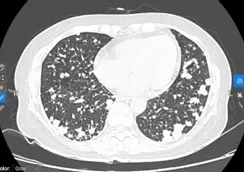

BN nữ P.T.H, sinh năm 1967, nhập viện vào thời điểm tháng 04/2024 vì lý do ho khan kéo dài, khó thở khi gắng sức, kèm theo đau nhiều cột sống ngực, thắt lưng. Kết quả kiểm tra ban đầu cho thấy hình ảnh tổn thương u phổi nhiều khối lan toả 2 phế trường, kèm theo di căn xương đa ổ. Kết quả sinh thiết vào vị trí u thuỳ dưới phổi phải là ung thư biểu mô tuyến phổi, xét nghiệm giải trình tự gen thế hệ mới NGS phát hiện đột biến xoá đoạn trên exon 19 gen EGFR (del19/EGFR). Bệnh nhân được lựa chọn liệu pháp nhắm đích ưu tiên là thuốc nhắm đích EGFR-TKI thế hệ 3, sau 6 tuần điều trị, tổn thương phổi 2 bên đáp ứng gần hoàn toàn trên CLVT ngực, bệnh nhân giảm đau rất nhiều tại tổn thương di căn xương cột sống, có thể sinh hoạt đi lại được, hoàn toàn không còn triệu chứng cơ quan hô hấp như ho hay tức ngực, khó thở.

Hình 6: tổn thương phổi trước điều trị